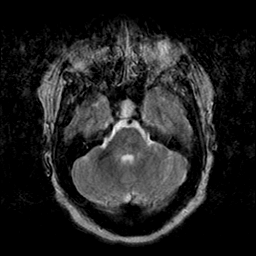

Cerebral hemorrhage, MR Study mr-t2 -- Slice #7

[Home][Help][Clinical] Slice 7